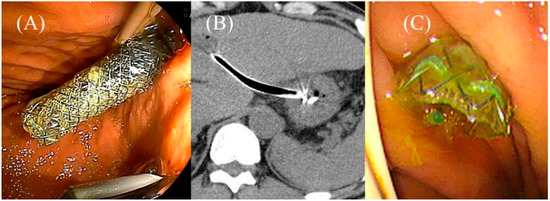

- Miyano, A.; Ogura, T.; Yamamoto, K.; Okuda, A.; Nishioka, N.; Higuchi, K. Clinical Impact of the Intra-scope Channel Stent Release Technique in Preventing Stent Migration During EUS-Guided Hepaticogastrostomy. J. Gastrointest. Surg. 2018, 22, 1312–1318. [Google Scholar] [CrossRef]

- Uchida, D.; Kawamoto, H.; Kato, H.; Goto, D.; Tomoda, T.; Matsumoto, K.; Yamamoto, N.; Horiguchi, S.; Tsutsumi, K.; Okada, H. The intra-conduit release method is useful for avoiding migration of metallic stents during EUS-guided hepaticogastrostomy (with video). J. Med. Ultrason 2018, 45, 399–403. [Google Scholar] [CrossRef]